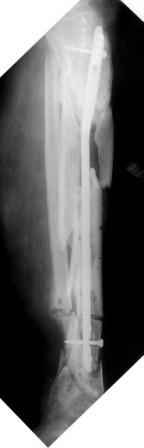

3) Третьим этапом наложили модуль на промежуточный фрагмент.(рис 3) И начали его транспорт на стержне в проксимальном направлении. (рис 3 а)

Надеемся что «вырастет» регенерат в дистальном отделе, а в проксимальном отделе фрагмент «упрется» и прирастет.